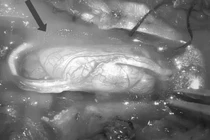

Với sự hỗ trợ của kính vi phẫu hiện đại, các bác sĩ bệnh viện Đa khoa Bãi Cháy đã thành công lấy toàn bộ khối u tủy kích thước lớn 20x30mm chiếm chọn ống sống, bảo vệ an toàn cấu trúc tủy sống và rễ thần kinh cho bệnh nhân 24 tuổi. Đây là bệnh lý rất nguy hiểm cần phải được phát hiện và điều trị sớm.